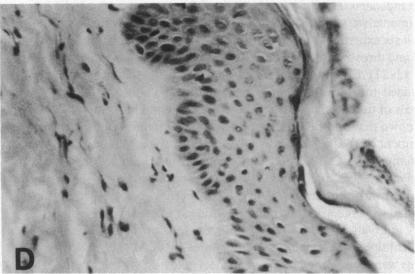

Stratification of human epidermal cells into multilayered sheets composed of basal and suprabasal layers (resembling the stratum germinativum and stratum spinosum of the epidermis) was studied in a dermal component-free culture system. Although no stratum corneum developed in vitro, this culture system provided a method to study early events in human keratinocyte differentiation. Multiparameter flow cytometric analysis of acridine orange-stained epidermal cells from these cultures revealed three distinct subpopulations differing in cell size, RNA content, and cell cycle kinetics. The first subpopulation was composed of small basal keratinocytes with low RNA content and a long generation time. The second subpopulation consisted of larger keratinocytes, having higher RNA content and a significantly shorter generation time. Finally, the third subpopulation contained the largest cells, which did not divide, and represent the more terminally differentiated keratinocytes. This in vitro approach provides discriminating cytochemical parameters by which the maturity of the epidermal cell sheets can be assessed prior to grafting onto human burn patients.